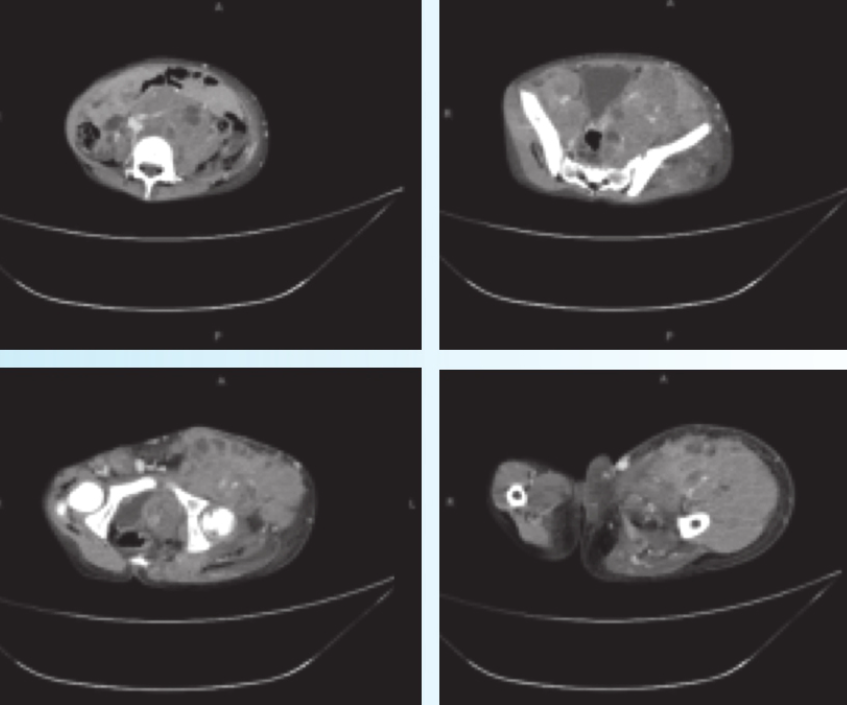

CT(图1):示下腹部、盆腔及左侧臀部、股骨周围见大片混杂密度影,形态不规则,内部见多发囊变坏死区,增强后呈明显不均匀强化。病变包绕血管,直肠和膀胱受压推移,子宫及附件显示不清。周围软组织水肿。左侧髋关节在位,髋关节及股骨形态尚可,未见明显骨质破坏。右腹股沟区多发肿大淋巴结。

图1 腹盆腔横纹肌肉瘤CT图像下腹部、盆腔及左侧臀部、股骨周围大片软组织密度影,符合横纹肌肉瘤改变;右侧腹股沟区淋巴结增大。